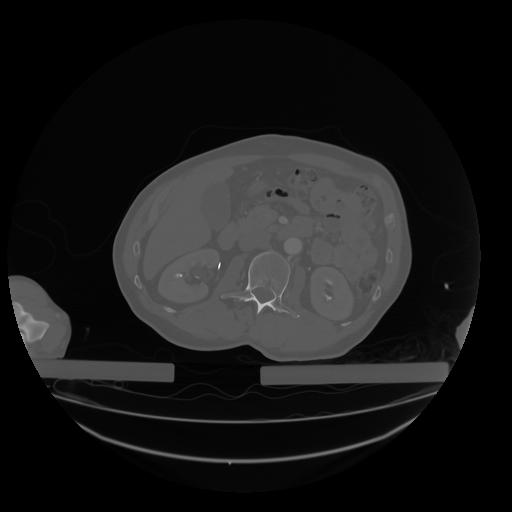

28 CUERPO,CE,Vol,2.0,CUERPO,,